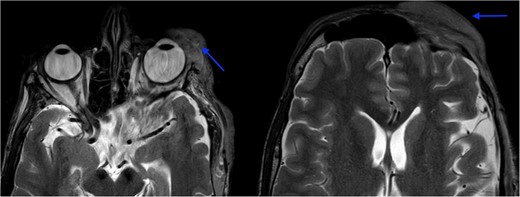

MRI revealed multiple nodular skin lesions over the scalp, suggesting neurofibroma (Fig. 2). The patient was operated on for surgical debulking under general anesthesia. Intra-operatively, neurofibromatous tissue was meticulously identified and dissected, while preserving the underlying peri-orbital musculature (Fig. 3).

MRI orbit revealed enhancing skin thickening over the left frontal region, maxillary region, temporal region, supraorbital region, and over the left eyelids covering the eye.